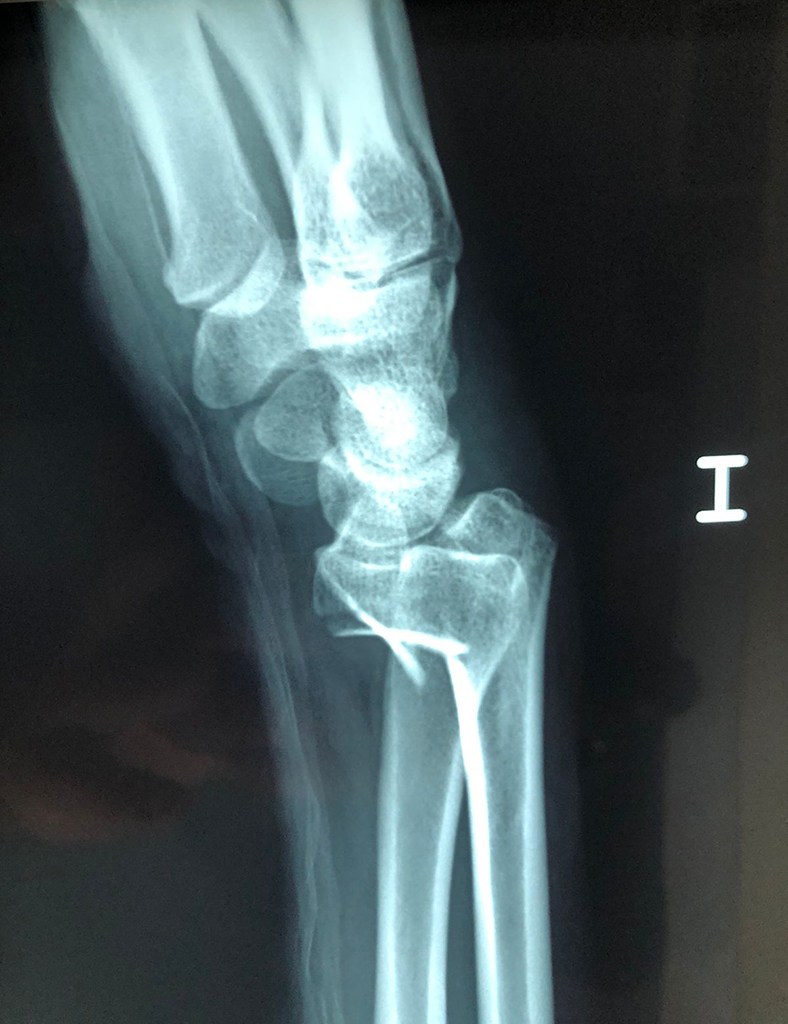

Cirugías de Muñecas

Los procedimientos más comunes en cirugía de la mano son aquellos destinados a reparar traumatismos, incluyendo lesiones de tendones, nervios, vasos sanguíneos, y articulaciones; huesos fracturados; y quemaduras, cortes, y otros daños de la piel.